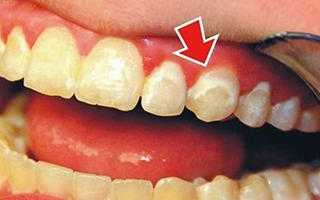

Фото 1. Снимок зубов взрослого человека с прогрессирующим на них кариесом начальной стадии.